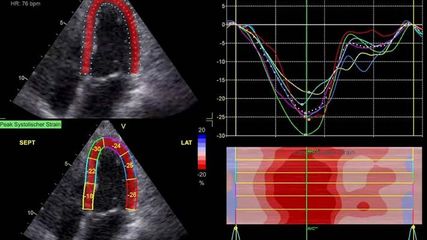

Stellenwert der kardialen Bildgebung bei Kardiomyopathien

In einem Beitrag aus Österreich am diesjährigen europäischen Kongress für Kardiologie (ESC) wurde über das große diagnostische Potenzial der modernen kardialen Bildgebung und die ...